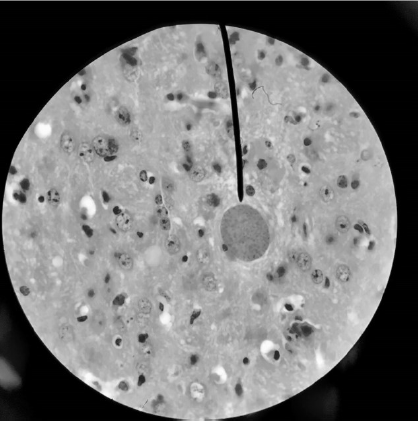

A imagem abaixo representa um achado obtido a partir da análise histológica de amostra de tecido nervoso de camundongo infectado com Toxoplasma gondii, em modelo de toxoplasmose experimental.

Fonte: Laboratório de Biologia da Malária e Toxoplasmose/DMP/CB/UF RN ( 2021)

A forma biológica apontada pela seta do microscópio corresponde ao